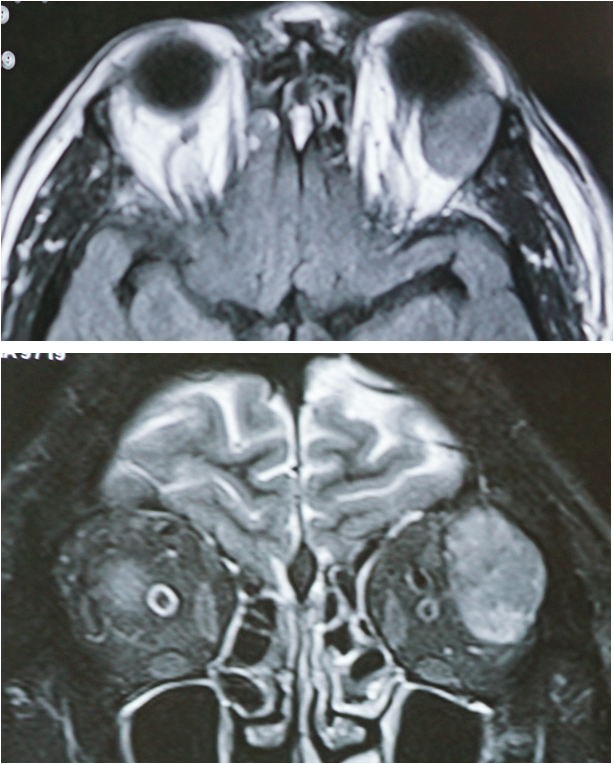

ORBITAL SURGERY

• Tumors

• Medical and surgical management

• Vision preservation